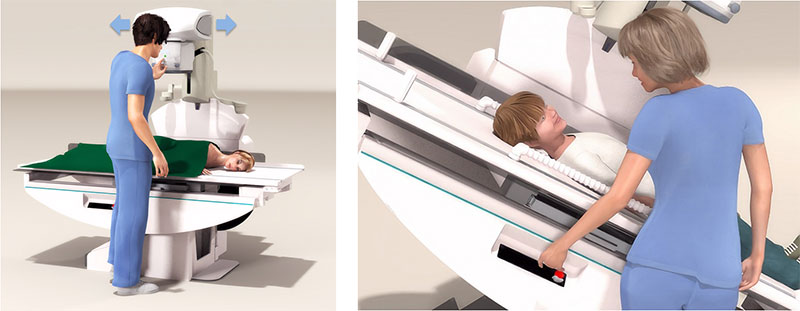

人性化的设计

精心设计、充分考虑用户需求。

近台控制及遥控控制的床体操作方式,可以应用于各种复杂检查。

操作更加方便,避免病人过度紧张,增加检查的成功率。

高效舒适的操作流程

Neo-Vision产品使用了轻便,可移动的无线动态平板探测器。可以轻松的进行透视及普通X射线摄影的切换。